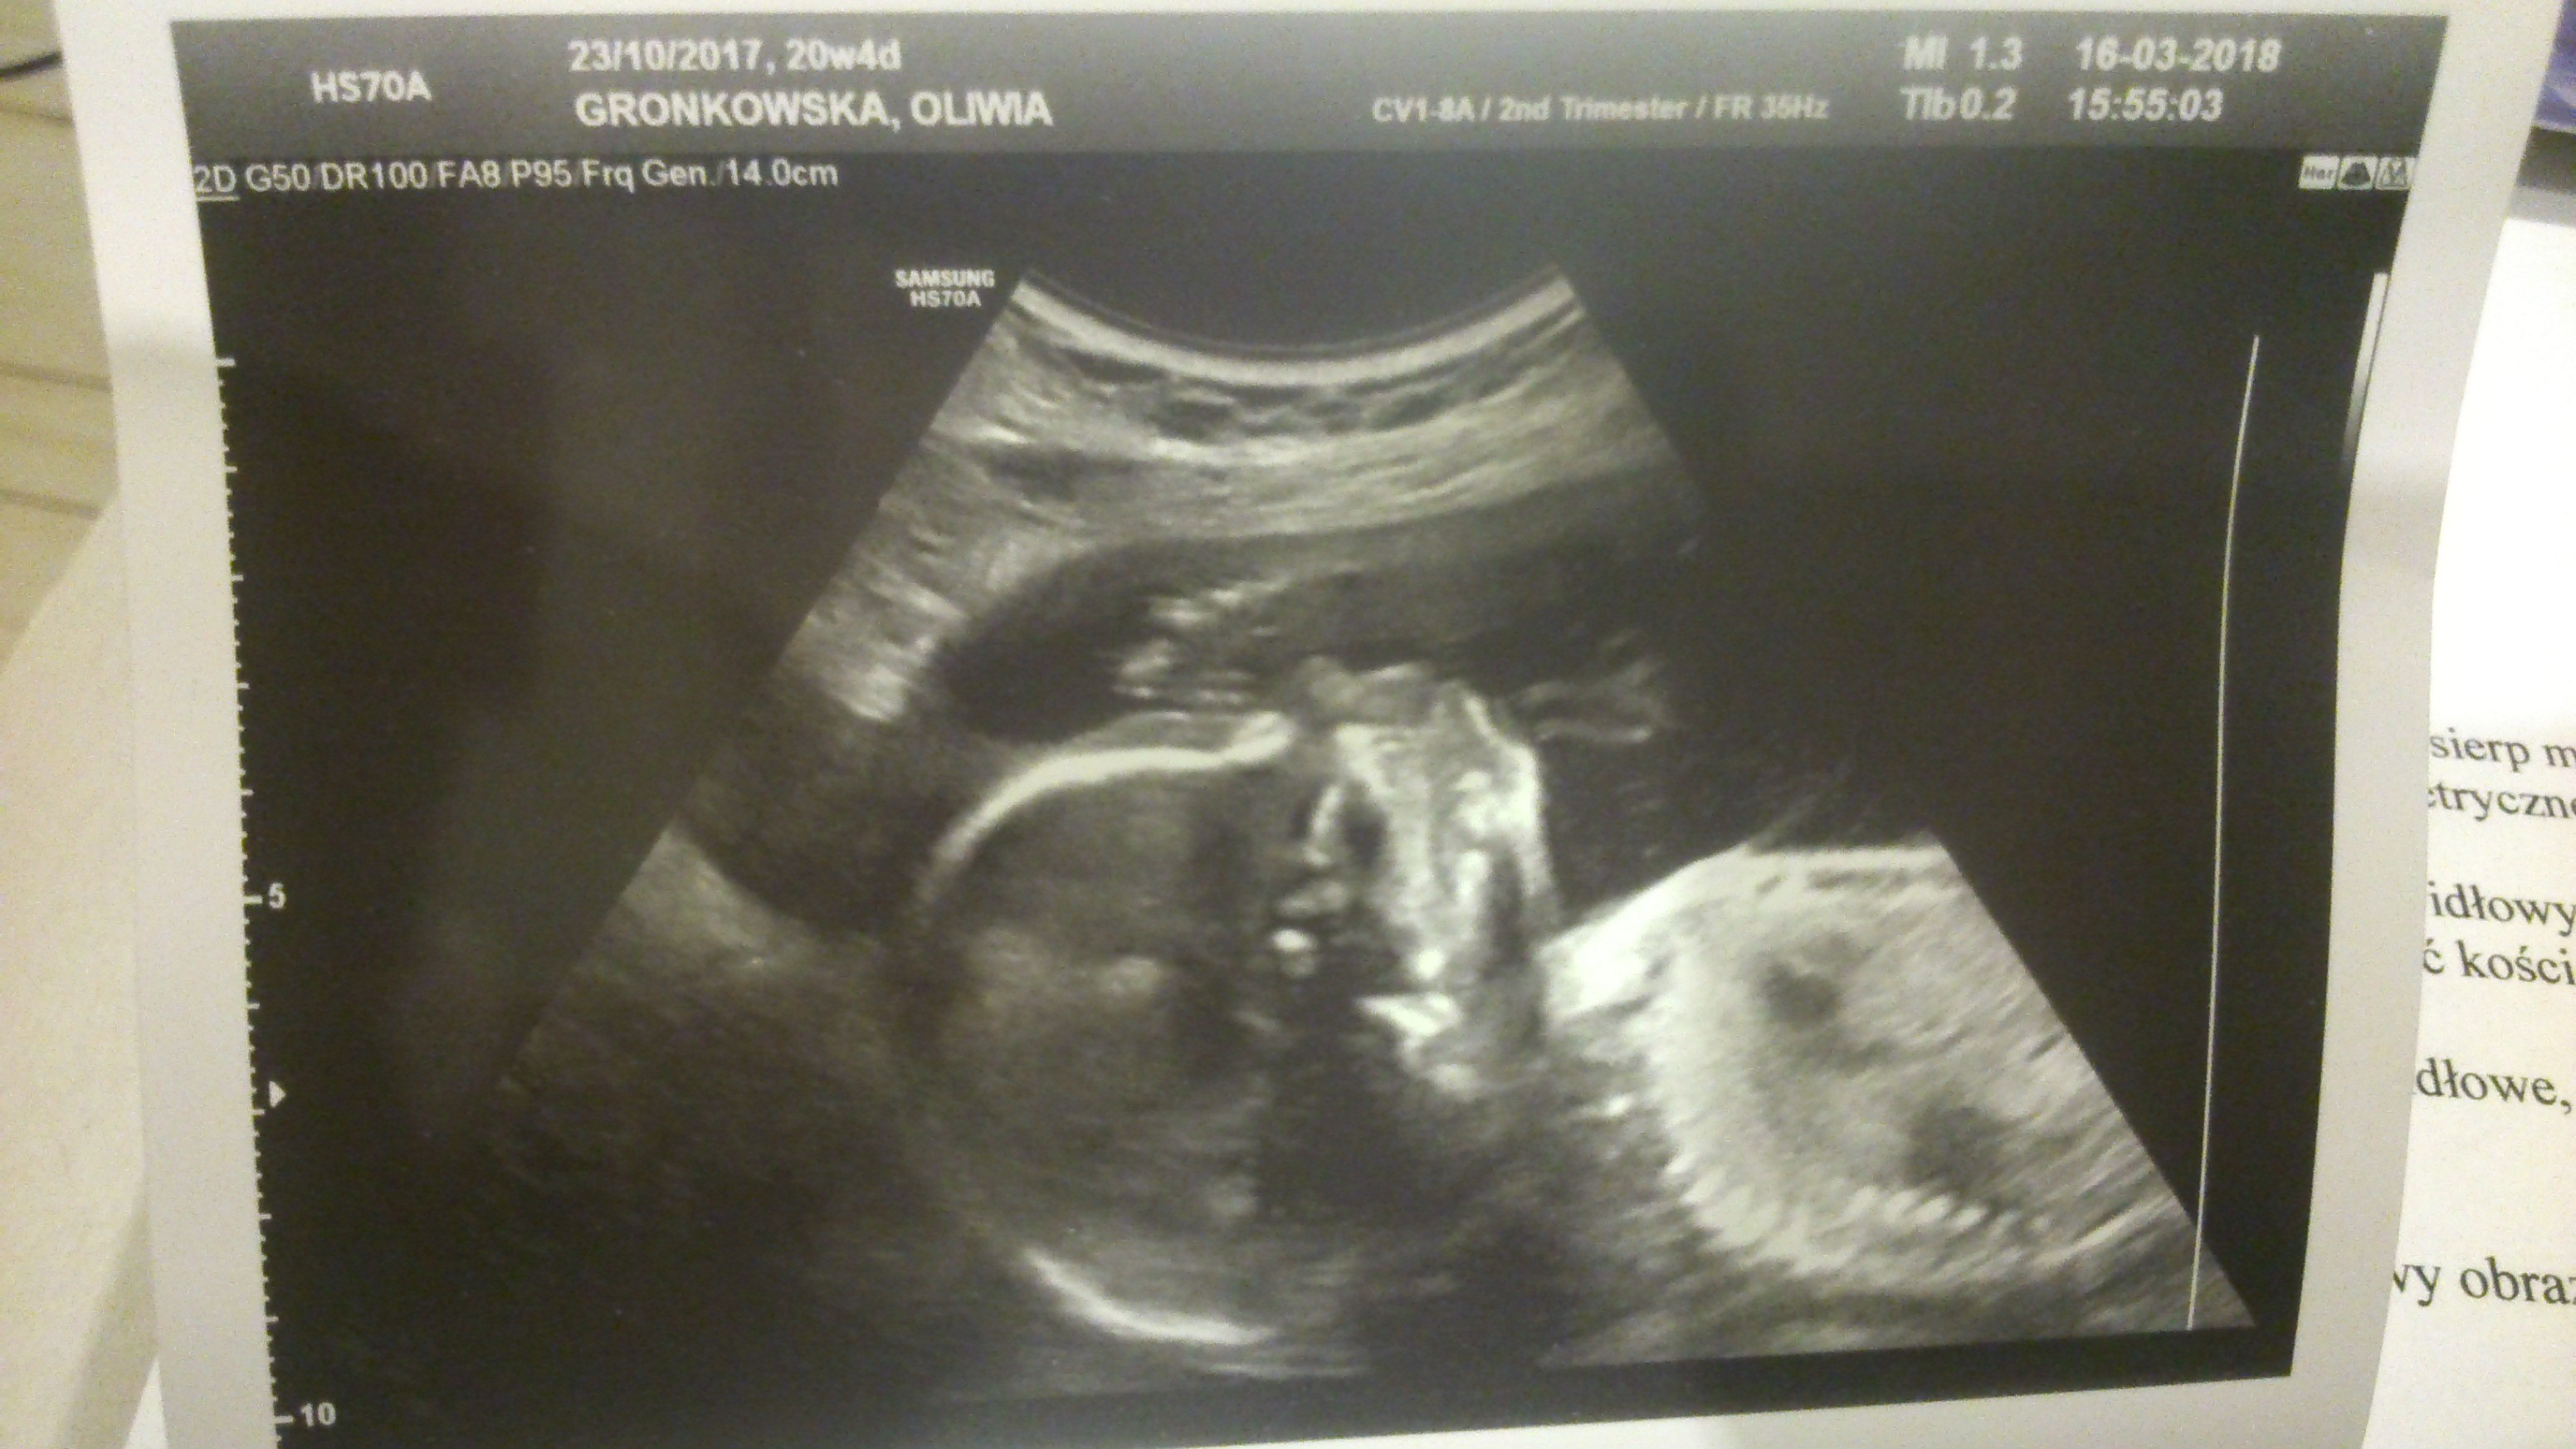

Ułożone są, jak to ona określiła? Podłużnie miednicowo, czyli są dupkami do dołu, zwrócone do siebie twarzyczkami :) Jedną udało się uchwycić w 3D, ale nie drukowaliśmy. Ważą praktycznie tyle samo: 354g i 359g ile mają cm nie wiem, bo dzisiaj tego nie mierzyła. No i termin z USG zmienił się z 31 lipca na 3 sierpnia :D Jestem mega happy.

Dodam, że lekarka mi powiedziała, że dziewczyny są tak podobne wagowo, że jakby się sklonowały. Fajnie w ogóle wyglądała przegroda owodniowa, jakby falowała jakaś nitka. A i foteczki mam buziolków :) i muszelek. Jedna akurat otwarła dziubek, to wygląda dziwnie.

Ja juz po wizycie dzidzia waży 375 g. Oczywiście nie chciała się dobrze rozkraczyć :-D tydzien temu lepiej się pokazała i wtedy lekarka powiedziała że ewidentnie dziewczynka, dzisiaj inna lekarka tez powiedziała ze raczej dziewczynka. Ale ja pewności nie mam ze tak na 100 % po usg w 30 tygodniu jak się znowu potwierdzi to uwierzę, nie dowiarek ze mnie :-D w razie co to mam i różowe ubranka, neutralne, lub chłopięce niebieskie także będzie miało w czym chodzić nawet jak będzie pomyłka :p

Usg miałam przez brzuch potem dopochwowo żeby zbadać szyjkę czy jest ok. Mała nawet buzi bardzo nie chciała pokazać co chwilę się drapala po nosie albo przy twarzy rączka .3 d nie robiła bo za bardzo się kręciła albo zasłaniala także ładne by nie były. Nawet te zwykłe fotki są słabe. Po usg poszłam do lumpeksu i kupiłam kilka ubranek :-)

No to już spora dziewuszka [emoji4][emoji4] moja w 17 tygodniu 4 dniu jak byłam na usg to ważyła 220 g i miała 12 cm i była dziewczynką. Zobaczymy co powie lekarz w przyszłym tygodniu na tym polowkowym. Mam nadzieje, że nadal będzie to dziewczynka, bo jak widać ja już zakupy przystosowałam do tej płci.